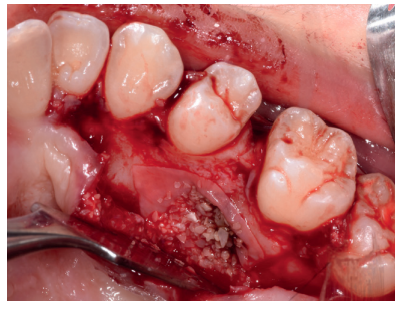

Caso clínico: se presenta un caso clínico de una mujer de 20 años, sin antecedentes médico-quirúrgicos de interés, que acudió a consulta remitida por su ortodoncista, para la extracción de un premolar maxilar retenido, en posición invertida. Tras la extracción del premolar y del tercer molar inferior retenidos, se obtuvo dentina procedente de ambos, para la regeneración ósea guiada del defecto resultante de la extracción del premolar, realizando revisiones a la semana y a los 4 meses de la intervención.

Clinical case: a clinical case of a 20-year-old woman is presented, with no interesting medical record, who went to dental clinic for removal of an inverse maxillary bicuspid retained. After maxillary bicuspid and lower third molar extractions, autogenous dentin was obtained from both teeth, to perform a guided bone regeneration of the bicuspid defect. A week and 4-month check-up were carried out.